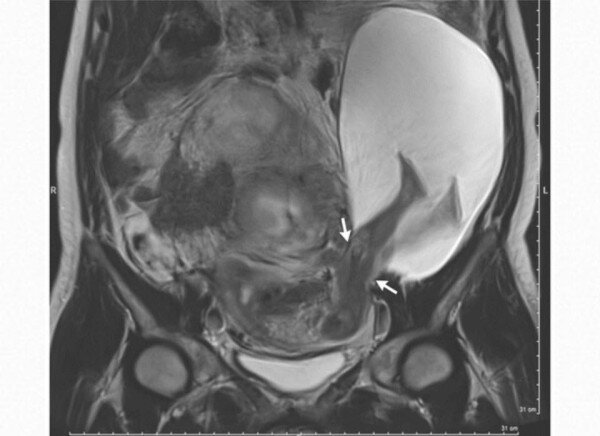

Пациентку ничего не беспокоило. При проведении УЗИ на 22-й неделе случайно обнаружили расхождение рубца на 2,5 см(полный спонтанный гистопатический разрыв матки), амниоцеле размерами до 19 см с ножками, а затем и другими частями плода. Не знаю, как поступили бы наши акушеры. Французы проинформировали пациентку и ее партнера о возможных рисках. А риски там - о-го-го! Как минимум "мы все умрем", включая полный разрыв матки, приращение плаценты, матки и преждевременные роды. Было принято решение пролонгировать беременность при тщательном контроле. Повторное УЗИ провели в 30 недель. Это тщательный контроль? Мы бы уже заузикали женщину до смерти! Разрыв матки увеличился до 5 см, в амниоцеле уже вывалилось полребенка. Наконец-то женщину прооперировали, извлекли живого недоношенного мальчика весом 1385 г. Матку зашили и оставили, выписали на пятые сутки в удовлетворительном состоянии. Это публикация французских акушеров-гинекологов от 22.12.16 года. Приходите дружить в Телеграм и ВК, там квиз

Было принято решение пролонгировать беременность при тщательном контроле. Повторное УЗИ провели в 30 недель. Это тщательный контроль? Мы бы уже заузикали женщину до смерти! Разрыв матки увеличился до 5 см, в амниоцеле уже вывалилось полребенка. Наконец-то женщину прооперировали, извлекли живого недоношенного мальчика весом 1385 г.

Матку зашили и оставили, выписали на пятые сутки в удовлетворительном состоянии.